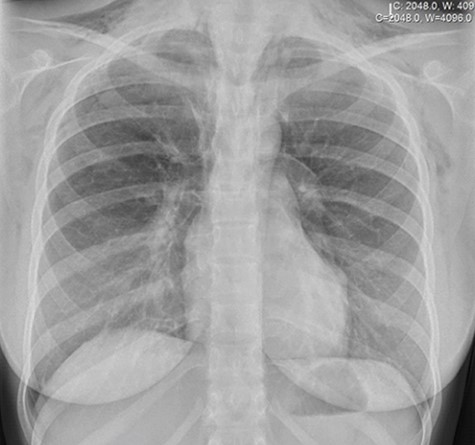

An urgent chest X-ray revealed extensive bilateral subcutaneous emphysema throughout the thorax and base of the neck with no visible pneumothorax or pleural effusion (Fig. 1). Thoracic and cervical computed tomography (CT) with contrast revealed a moderate pneumomediastinum and extensive subcutaneous emphysema throughout the neck, supraclavicular fossae, axillae and upper chest wall with no overt evidence of esophageal injury (Fig. 2).

Chest X-ray demonstrating pneumomediastinum with associated subcutaneous emphysema.